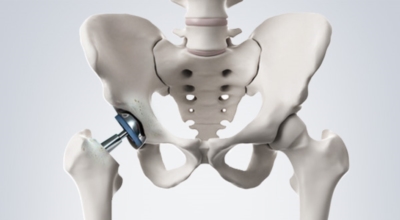

고관절 통증 증상 치료법

고관절 통증 치료에는 크게 약물 치료와 물리 치료가 있답니다. 고관절염의 진행을 늦추거나 증상을 개선하기 위한 목적으로 항염증제 또는 진통제를 투여해요. 고관절 질환의 일부 증상은 체외 쇼크파, 물리치료, 약물치료 과 같은 비수술 요법으로 증상이 호전될 수 있습니다.

그러나 비수술 치료법으로 개선시키는 것이 어려운 경우 수술적 방법이 고려되어요. 고관절 통증을 조기에 치료하면 약물치료 외에 물리치료로 약 50% 정도 큰 효과를 볼 수 있답니다. 게다가, 보통 고관절 증상 관리에 보탬이 되는 요가, 수영, 스트레칭은 고관절 예방과 치료에 보탬이 돼요.